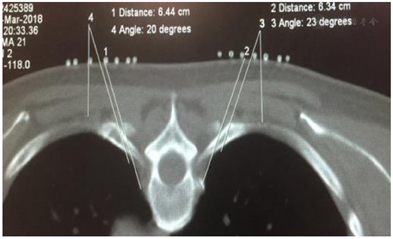

"CT引导下胸交感神经射频技术"已在嘉兴市科技局立项并取得嘉兴学院附属医院伦理委员会批准(伦理编号:LS2018-141)。术前与患者详细讲解该技术的操作流程、可能的疗效与风险,取得患者知情同意后,禁食4 h,上肢静脉留置针开放输液通道,嘱患者俯卧于CT操作台上,暴露胸背部,胸下垫软枕。监测并记录患者的血压、心率、血氧饱和度、双手掌温度和末梢灌注指数(Pulse Index,PI)。在胸4椎体(T4)对应背部皮肤上放置定位栅,用CT定位像准确定位(T3-T4)椎间隙,并以之为中心对上下两个椎体进行层厚3mm扫描,找到第4肋骨小头(R4)上方裸露的层面(椎间孔外无肋骨、关节突、椎板遮挡)作为穿刺进针层面并在该层面上设计穿刺路径:靶点为第4肋骨小头上缘。用CT自带工具软件由靶点经第4肋椎关节上缘向皮肤拉直线,与皮肤交点即为穿刺进针点,测量出拟进针深度(进针点与靶点的距离)、进针角度(穿刺针与矢状面夹角),见图1。打开CT的激光定位红线,移动CT床至所选穿刺层面,用记号笔在定位红线上标示出两侧穿刺进针点,常规消毒铺巾后,用1%利多卡因对选定穿刺点进行局部麻醉,按照拟定的进针角度和深度于CT引导下进针:双侧用长10 cm、裸露端为10 mm的7号射频针经T3-T4椎间隙进针至T4肋骨小头上缘(图2,图3),拔出针芯,沿套管插入配套电极,进行90℃ 300 s射频热凝,见视频。